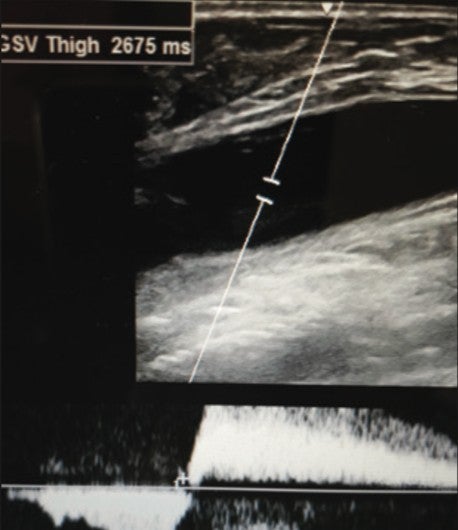

- Proximal GSV thigh: 2.5 seconds (Figure 1)

Figure 1. Pre-Varithena Treatment Rt. Prox. GSV Thigh: 2.5 seconds